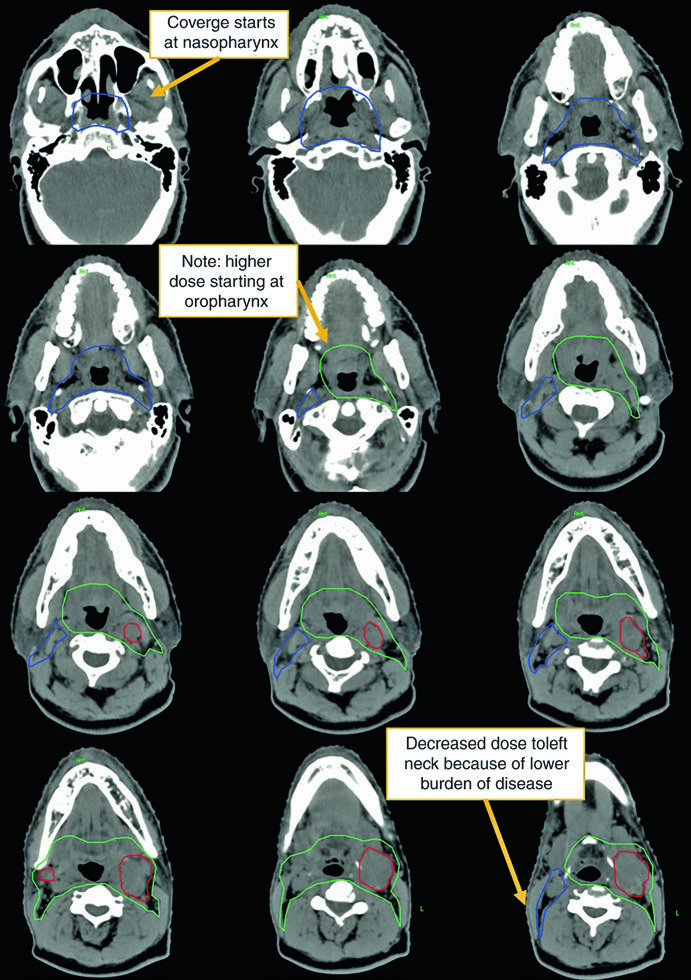

O segundo caso demonstra um cenário mais agressivo: homem de 50 anos com TxN2c, biópsia aberta de linfonodo à esquerda demonstrando extensão extranodal, HPV ISH e p16 negativos. Recebeu quimiorradioterapia definitiva.

Neste caso, o CTV70Gy (vermelho) engloba a doença macroscópica bilateral; o CTV60Gy (verde) cobre as mucosas faríngeas em risco; e o CTV54Gy (azul) inclui todo o pescoço bilateral profilaticamente. A negatividade para HPV justifica a cobertura abrangente de toda a faringe, pois sem a orientação viral para um subsítio específico, o risco é distribuído ao longo de todo o eixo mucoso.

A presença de ECE neste caso reforça a indicação de quimioterapia concomitante. A dose de 70 Gy na doença macroscópica e 54–60 Gy nas mucosas em risco segue o escalonamento padrão. Compare essa abordagem com as estratégias específicas para câncer de laringe, onde o foco é preservar a função laríngea.